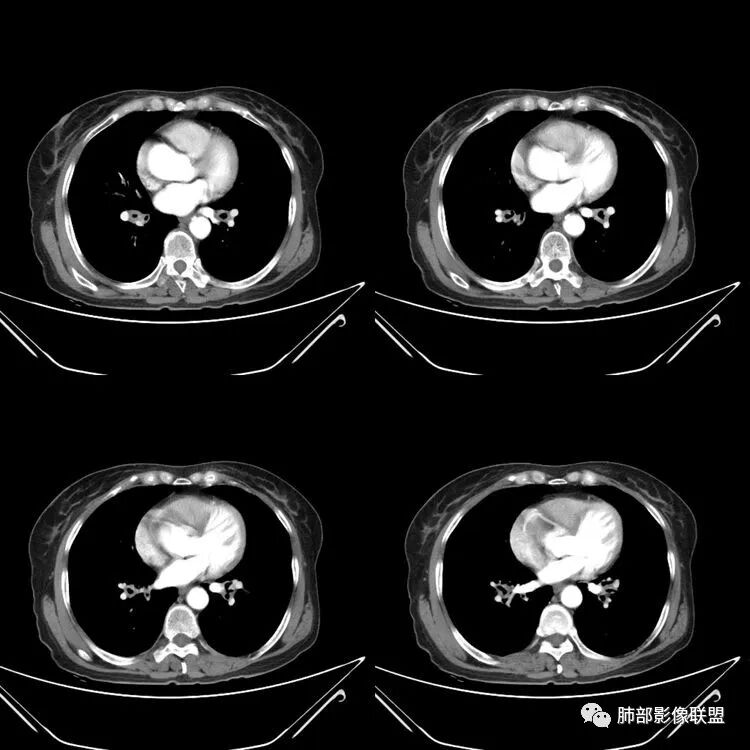

患者,女,64岁,反复咳嗽、咳痰、胸闷10年,加重2周。气管支气管及两肺下叶 支气管弥漫性的环状增厚,管腔扩张,管腔感觉比较松弛。第一感觉,气管支气管淀粉样变。鉴别诊断,1、支气管内膜结核,肺内散在一些支气管的播散病灶,粟粒结节为主,形态比较单一。2、复发性的多软骨炎,就得了解一下其他部位,有没有多个部位的软骨炎。这个病人右侧胸廓缩小,升主动脉明显的扩张,其横径明显的超过了降主动脉。

征象很明确

弥漫支气管壁增厚,膜部受累

声带肥厚——受累

隐约见钙化

南边:肺部有肺气肿支气管腔狭窄淀粉样变性?复发性多软骨炎?血管炎?慢支?结核?曲霉菌?南边:一般还是淀粉样变性与复发性多软骨炎鉴别其次就是支气管骨化症,但是骨化下朝上,且壁结节状钙化明显,本例不太支持。至于结核、曲霉菌?1.结核,一般不会这么广泛,支气管壁狭窄后扩张2.曲霉菌可以这么广泛,但是支气管壁管腔扩张,而且附近脂肪间隙有炎性反应,不太支持;3.血管炎,一般合并肺内有病灶,但是声带受累,放待排;4.软骨炎一般全身受累,例如耳廓等;而且膜部不受累,不太支持;倾向于淀粉样变性;淀粉分很多型,气管支气管是最常见的。尘缘:影像上生理性钙化与支气管骨化无法区别,镜检也不好鉴别,需要依赖活检,看粘膜中是否合并炎性改变(淋巴细胞,组织细胞等炎性细胞侵润)来鉴别Coke with ice:经常看到的这种是老年性肺改变,又称年龄相关肺改变。气管和支气管弥漫性软骨钙化,常见老年女性。尘缘:支气管骨化症很罕见的,所以绝大多数还是生理性钙化。对于老年人,无临床症状的钙化,还是基本上都是生理性钙化,无临床意义。大雄:如果管壁钙化伴明显增厚 影像还是提示一下建议支气管镜稳妥些

病理结果:肺淀粉样变

气管支气管淀粉样变性

三、影像表现

1.气管支气管型

①气管支气管壁增厚,形成粘膜下斑块与结节

②管腔广泛狭窄、闭塞

③管壁钙化

④膜部受累(具有重要鉴别意义)

---鉴别诊断

①骨化性气管支气管病

主要是由于气管支气管壁软骨化生及异位软骨瘤形成,气道膜部没有软骨,所以不累及膜部,气管壁结节样增厚伴钙化。

②复发性多软骨炎

多系统受累,常累及鼻、耳廓等其他部位的软骨,气道膜部没有软骨,所以膜部也不受累,气管及支气管壁平滑增厚,管壁钙化,管腔弥漫性缩窄,外壁模糊。